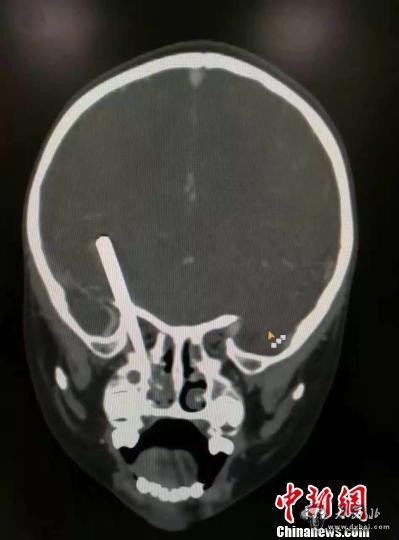

小宇的CT图。通过CT,能清楚看到筷子插入小宇颅内。 儿童医院供图 摄

医生通过小宇头颅CT片发现,这根“肇事”的筷子经小宇的口腔穿入,穿过右侧鼻腔、上颌窦、眼眶后部、视神经、进入右蝶骨小翼边缘部直插右侧额叶底部,插入体内约8cm,进入脑组织内约3厘米,小宇的右侧视神经被切断。